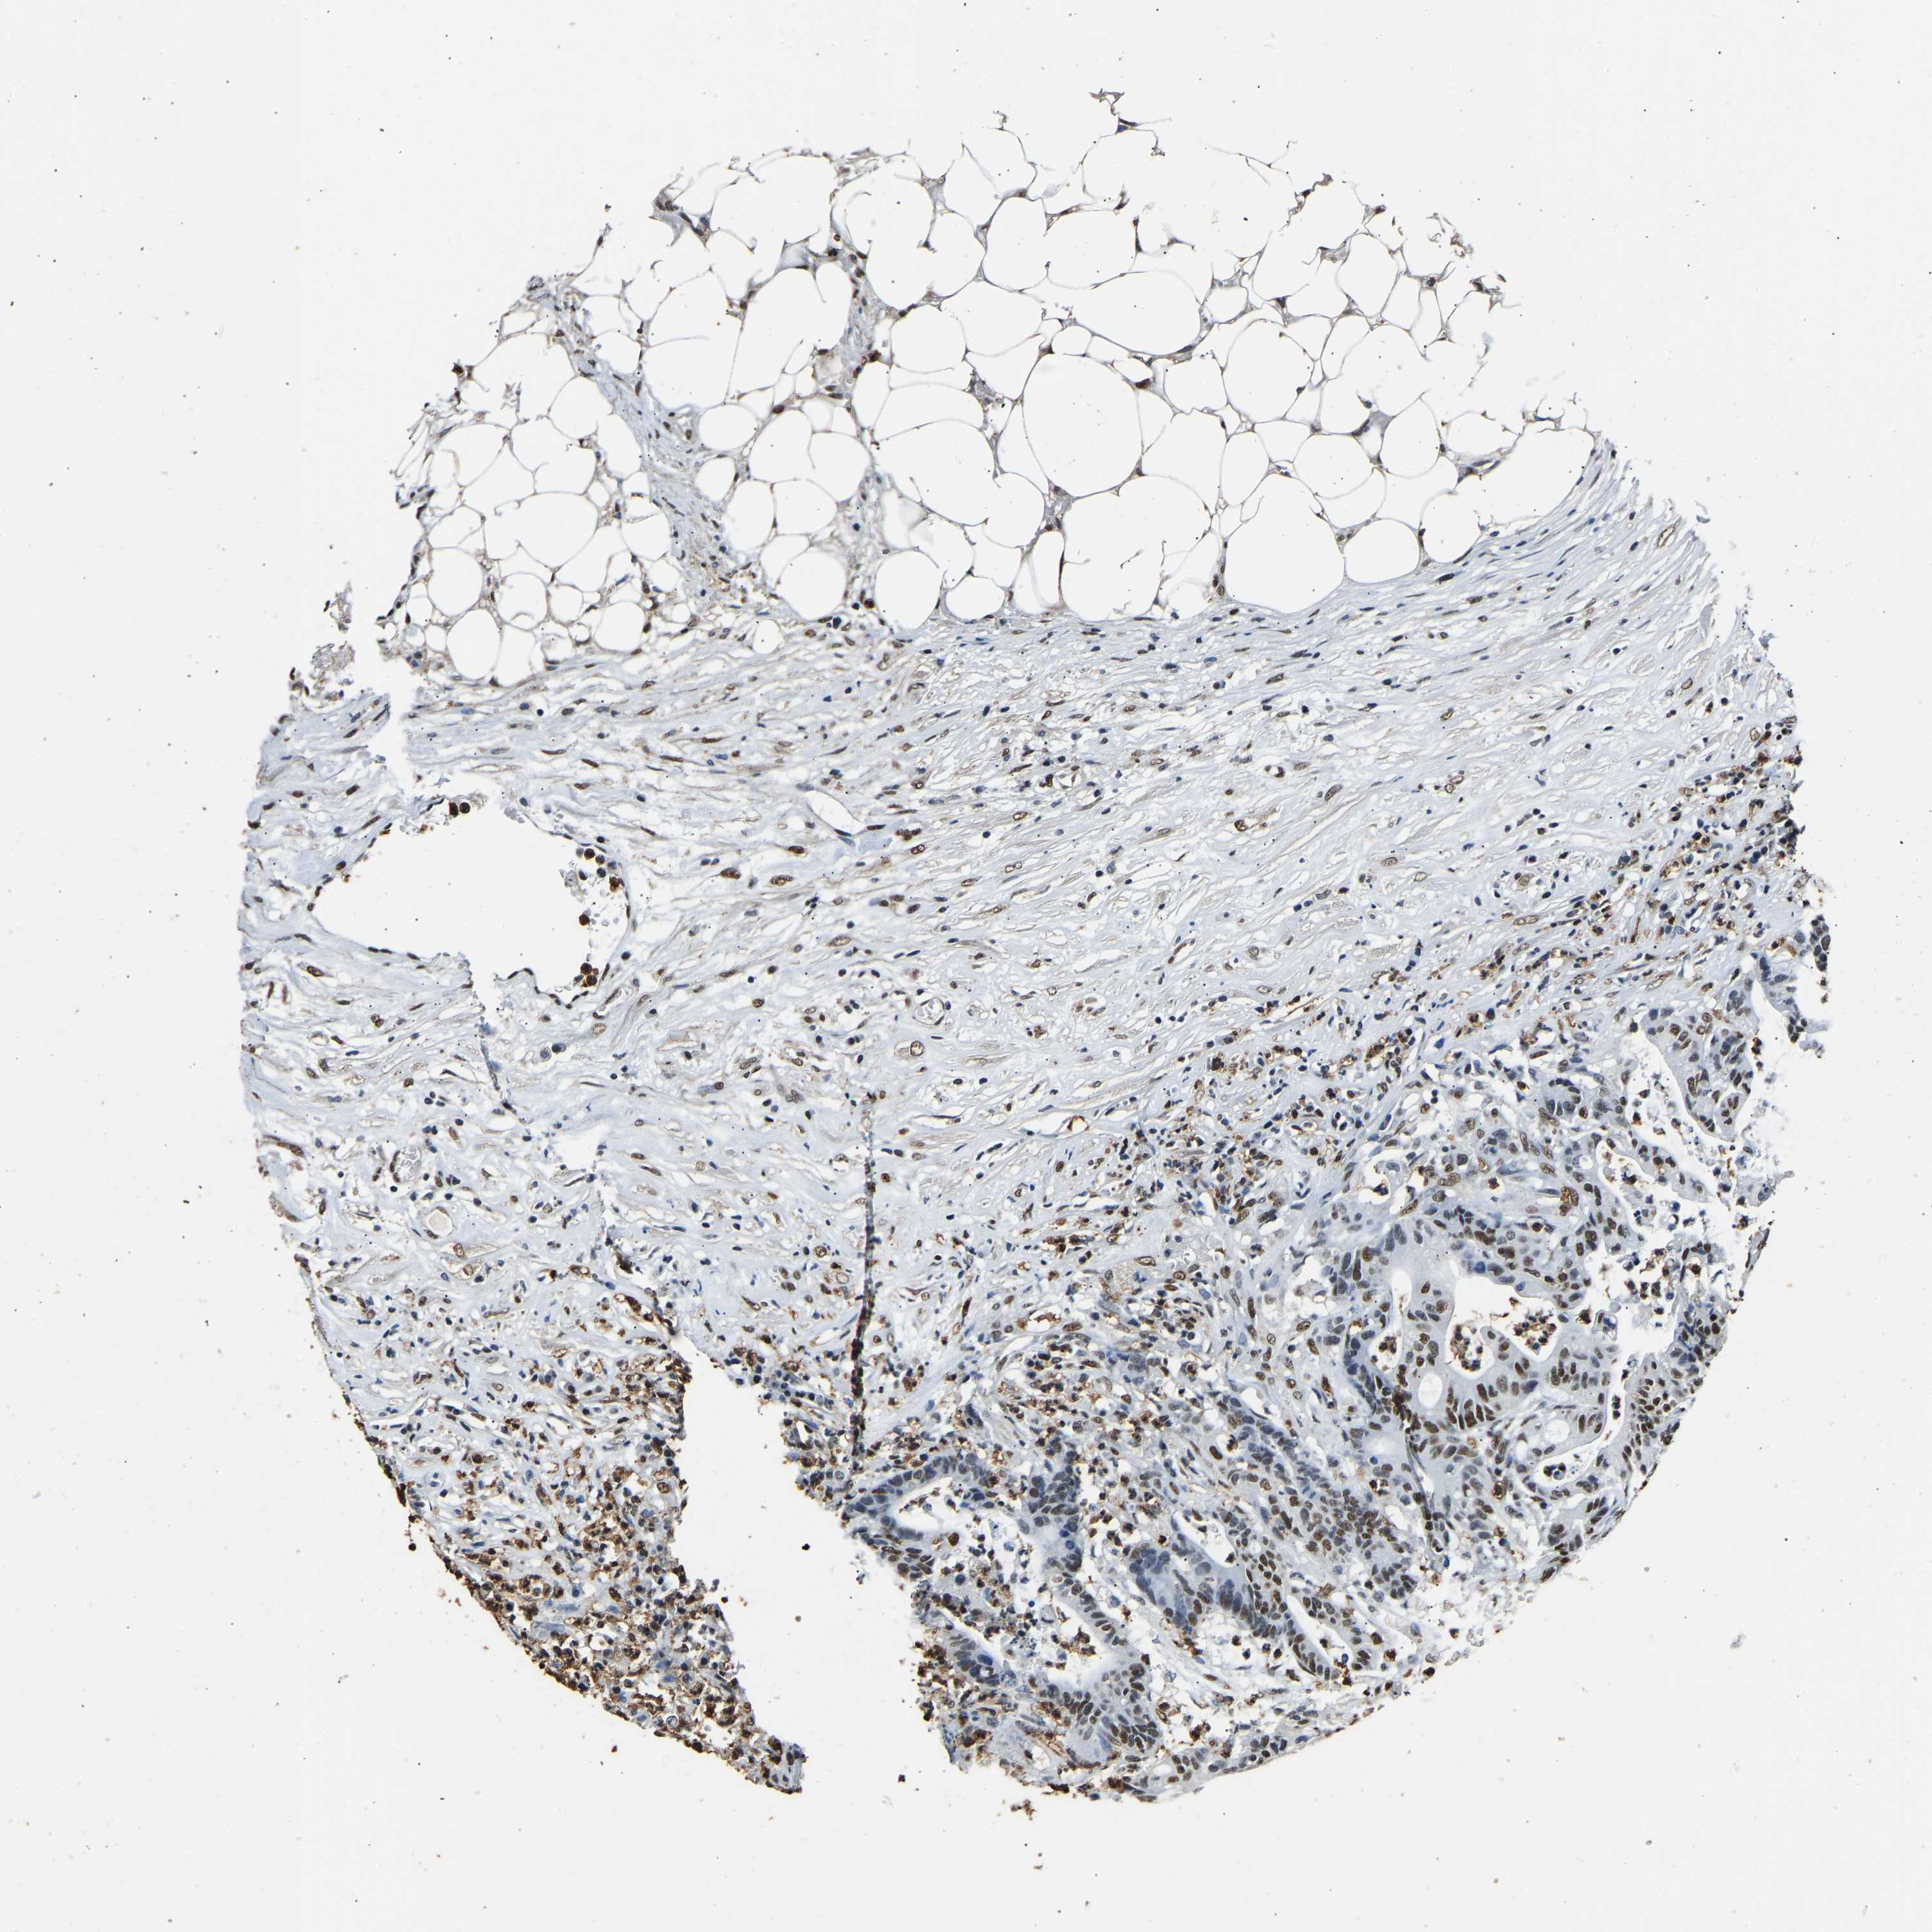

CANCER COLORECTAL CANCER Show tissue menu

Colorectal cancer

Human cancer